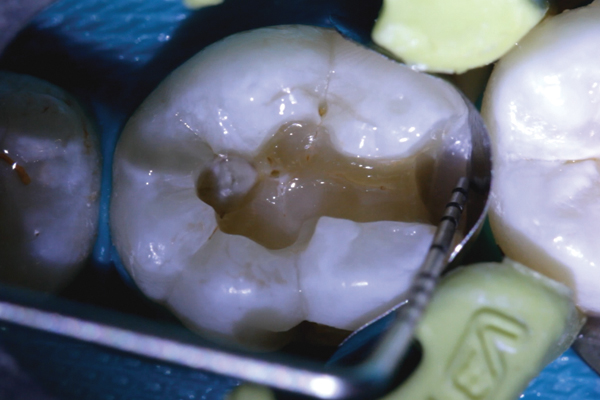

(4.) Preparation of tooth No. 19 with 4-mm distal box.

Figure 4

Higher viscosity bulk-fill composites can be used up to the occlusal surface, however. Two clinical cases using the bulk-fill composites Tetric EvoCeram Bulk Fill and SonicFill are presented in Figure 2 through Figure 6. Limitations when placing a high-viscosity bulk-fill composite include difficulty of condensing and esthetic restraints. Condensing a high-viscosity resin composite ensures adequate adaptation to the tooth preparation and sufficient interproximal contacts. Condensing 4 mm of composite is more difficult than condensing 2 mm. To ensure adequate interproximal contacts, a sectional or circumferential matrix with an inciso-gingival curvature can be used to obtain a tight area of contact gingival to the marginal ridge. A ring should be used to help separate the teeth and improve the tightness of the contact area.